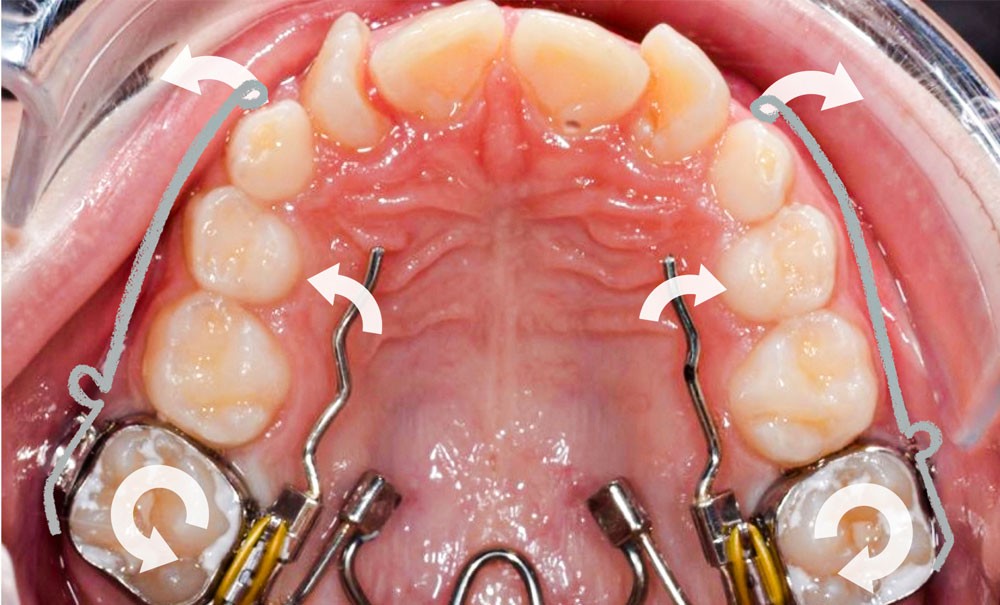

Des bagues molaires sont essayées et adaptées sur 16 et 26 et un arc transpalatin à mémoire de forme (Nitanium Palatal Expander -Ortho Organizers, USA) dont la dimension est sélectionnée à partir de la mesure de la distance inter-molaire mandibulaire est ligaturé à celles-ci hors bouche. L’ensemble est scellé avec un ciment verre-ionomère après refroidissement au spray à -45 °C de la partie en NiTi pour insertion facilitée.

Une fois que la partie en alliage à mémoire de forme de l’arc transpalatin a retrouvé sa forme initiale, l’arc est désinséré. Les U latéraux et les lames d’insertions en acier sont réglés dans les trois sens de l’espace à l’aide d’une pince 139 pour corriger l’inclinaison mésio-distale, le torque et augmenter la dérotation de 16 et 26 pour assurer une traction supplémentaire des canines incluses en direction vestibulaire. Les bras d’expansion des secteurs latéraux de l’arc transpalatin sont également sectionnés. Les bras vestibulaires en TMA sont activés dans le sens vertical pour une traction des canines vers le plan occlusal.